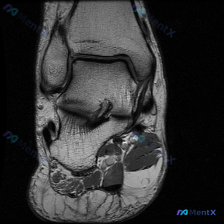

大家好,碰到一个很有讨论价值的阅片病例,整理了资料和分析思路分享给大家。 病例基础信息 这是一张踝关节MRI-T1序列冠状位单张影像,核心问题是:阅片者观察认为存在软骨异常,但影像系统分析未发现明确病理性改变。 影像基本评估结果 先给大家完整呈现这次的阅片结果: 1. 骨骼系统:胫骨远端、腓骨远端、...